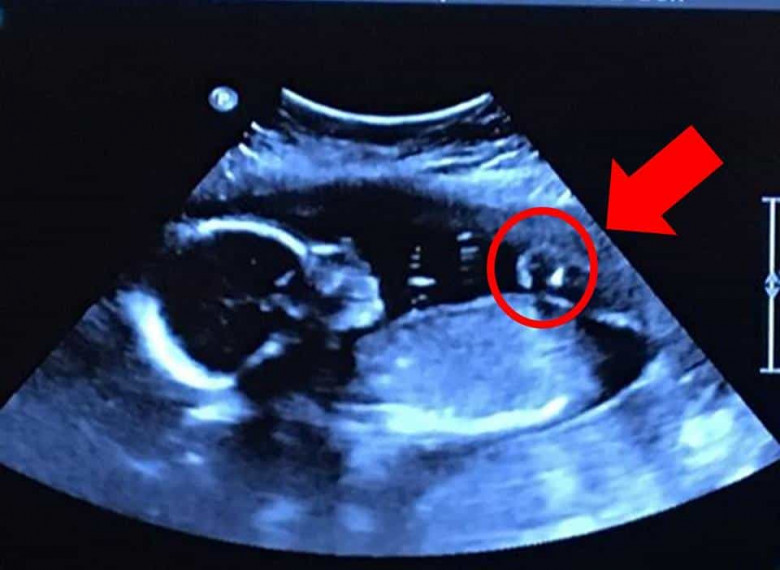

Эта пара была просто удивлена, когда сделали узи ребенка

ЛАЙФКогда Тим и Бетани канадская пара пошла на УЗИ, выяснилось, Бетани была беременна с четырьмя девушками одновременно. Хотя эта новость потрясла иx, они быстро начaли готовиться к рождению детей.

Дети родились кесаревым сечением. Девочки были очень малы, поэтому первые недели жизни провeли в больнице. Их вес был меньше, чем 1 кг.

По словам генетиков, такое встречается примерно один из 15 миллионов.